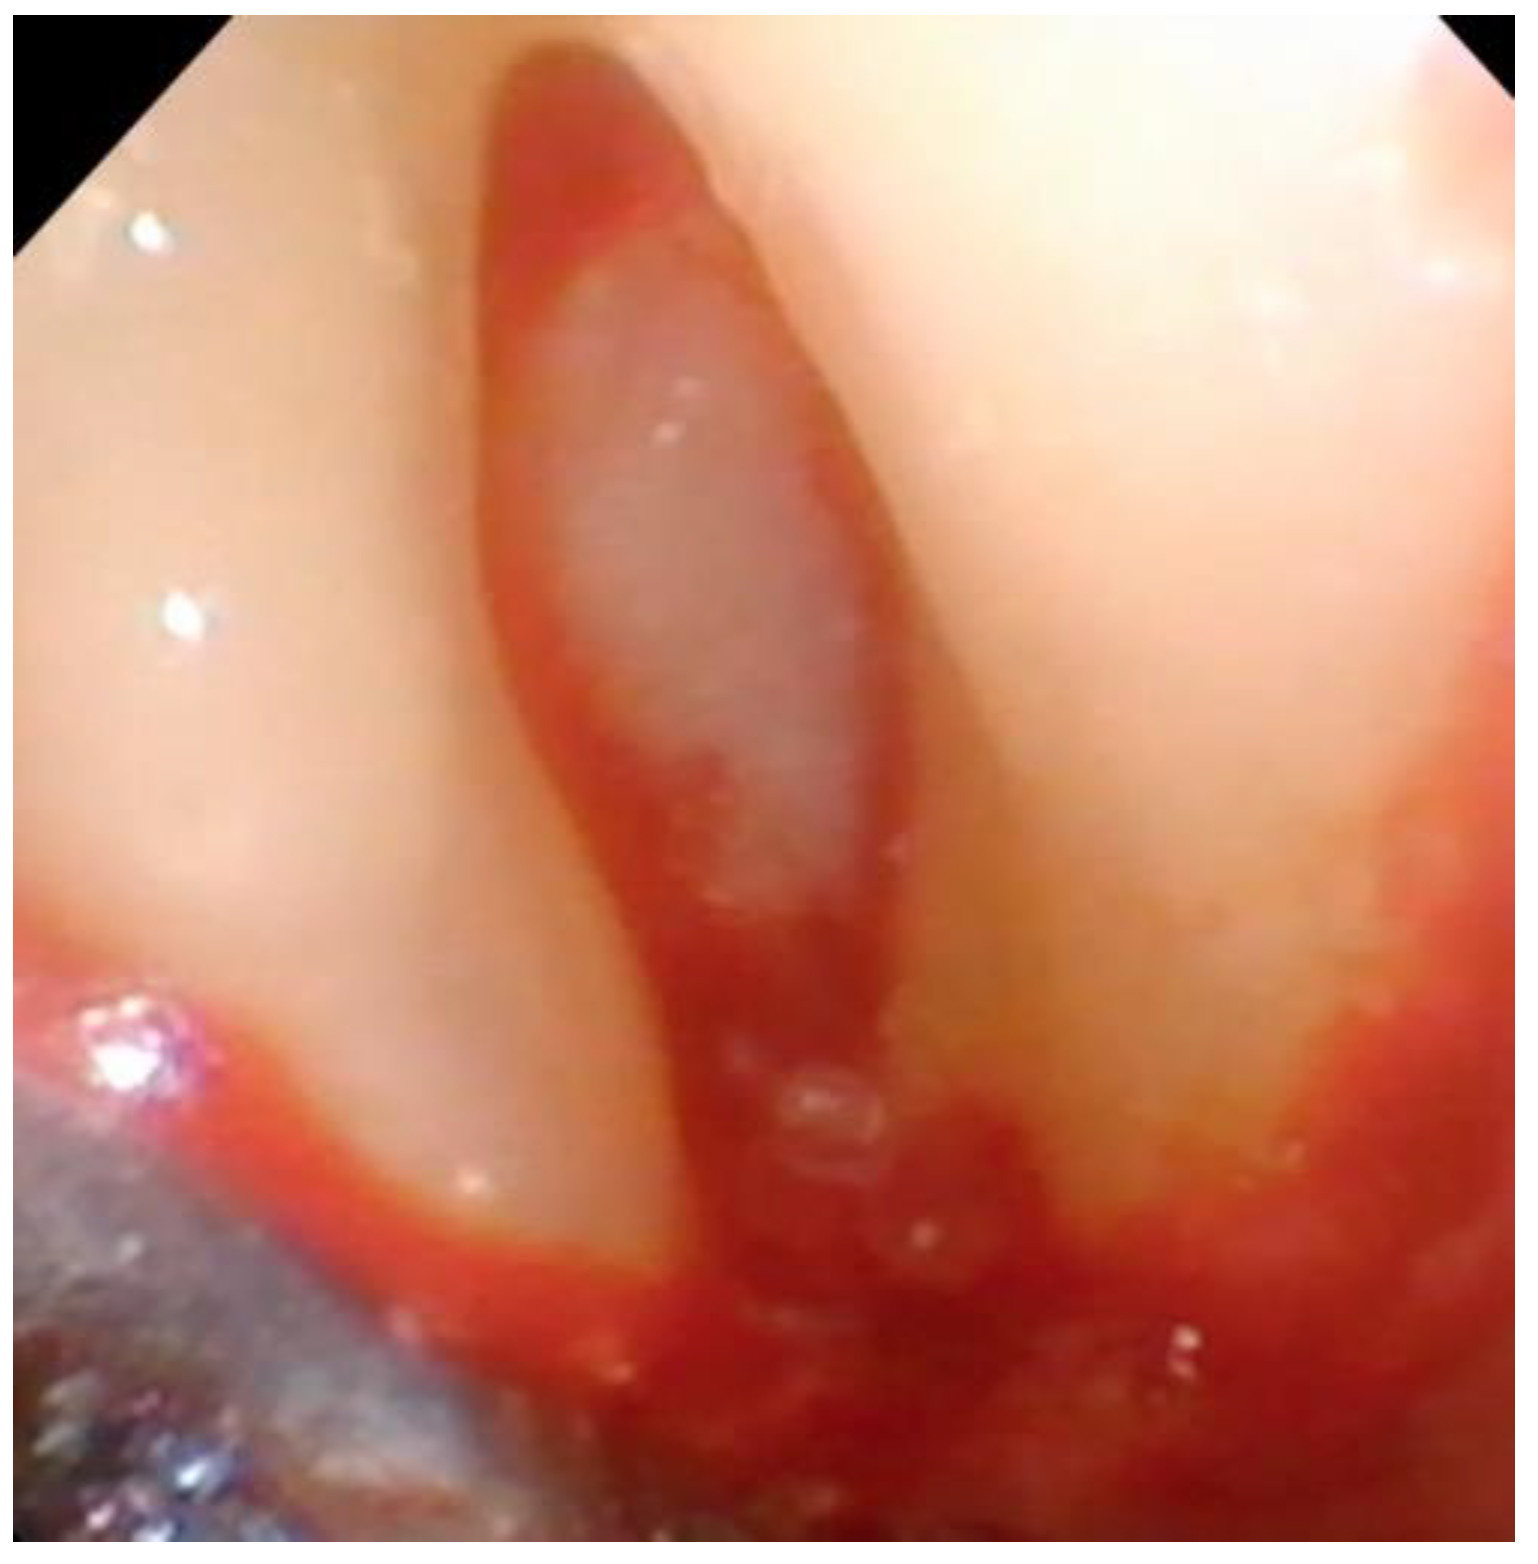

Figure 8. The fully debrided bony lesion can be visualized after removal of the granulation tissue.

Following the removal of the thin section of tissue, any granulation tissue is removed in a similar manner as performed on natural teeth. However, care should be taken to not touch the implant surface with the instrument used to remove the granulation tissue. The implant surface is covered by titanium oxide, and this has been shown to be an integral part of the osseointegration process [22]. Titanium oxide is very fragile and will be damaged or corroded if the implant surface is touched by an instrument or disinfected with harsh chemicals such as citric acid or a tetracycline solution. Because of this, great care is taken to not touch the implant with a curette while removing the granulation tissue and to only gently wipe the implant surface with sterile gauze soaked in saline. The debrided peri-implant bone loss is shown in Figure 8.